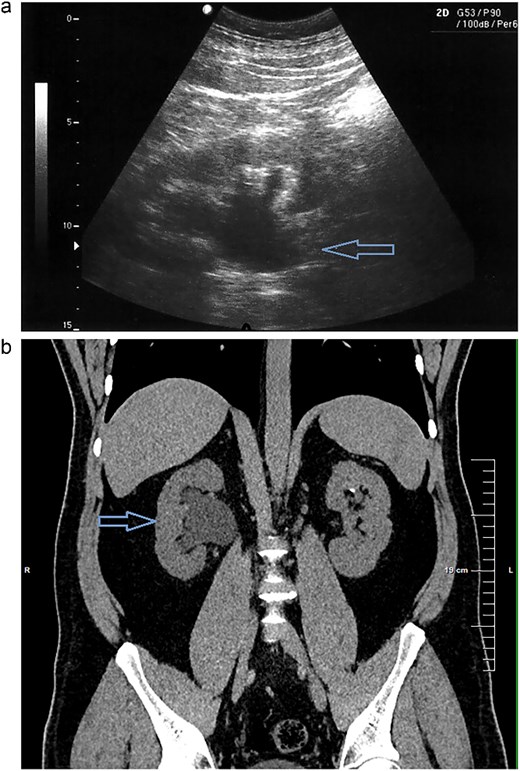

On presentation the patient reported pain in the right lumbar region, without fever starting 1 week prior to admission. The physical examination was unremarkable, except for positive right side Pasternacki's sign. Laboratory tests of full blood count, urinalysis and biochemistry were unremarkable, with the exeption of uric acid that was elevated 483 μmol/L (reference range 208–428 μmol/L) (Tables 1 and 2). Abdominal ultrasound demonstrated grade 2–3 hydronephrosis in the right kidney (Fig. 1a); a 4 mm calyceal stone, without obstruction in the left kidney. Initially, conservative therapy was started. A contrast-enhanced computed tomography (CT) scan of the abdomen and pelvis revealed bilateral calyceal nephrolithiasis and right-sided ureterohydronephrosis caused by a cluster of stones in the right distal ureter (Figs 1b, 2, and 3).

(a) Abdominal ultrasound demonstrating right kidney with evidence of grade 2–3 hydronephrosis. (b) Right kidney right-sided ureterohydronephrosis on CT scan.